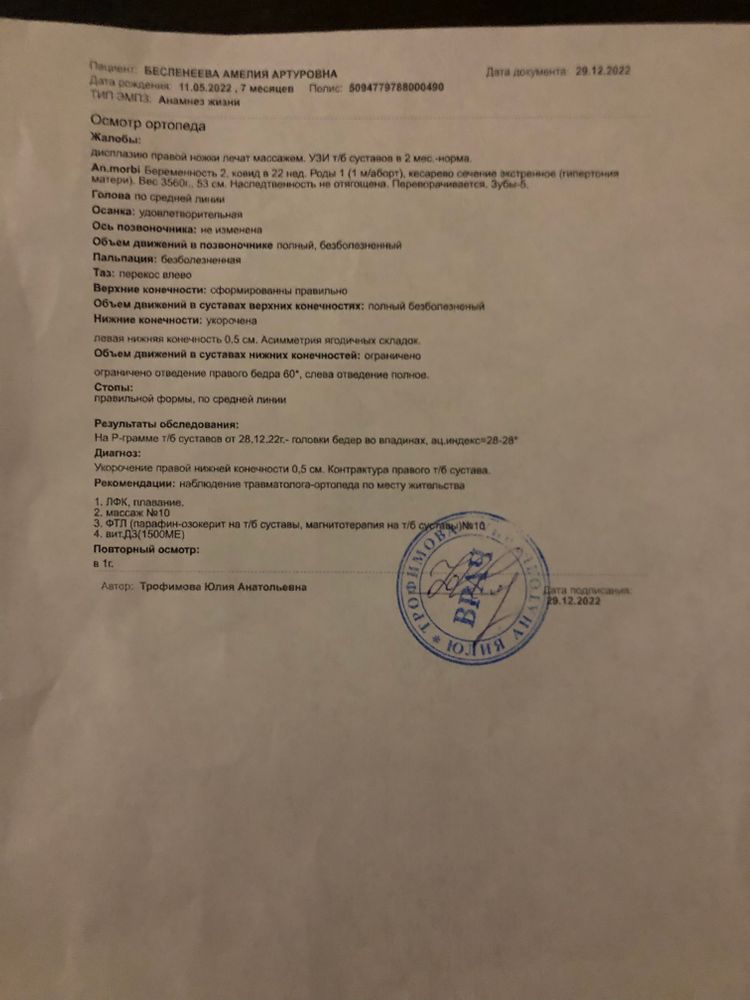

Малышке 7,5 месяцев, прошли второй курс массажа и на массаже мне сказали,что надо сходить к ортопеду,массажистке не понравилась правая ножка у малышки. Мы пошли к ортопеду,он осмотрел визуально нас,сказал,я ничего не вижу,но сходите на рентген. Пошли га рентген и там описали снимок,дали заключение вывих правого тазобедренного сустава ножки под вопросом. Дали нам направление на осмотр в клинике ортопедии и травматологии в Москве. Сегодня поехали туда,там нас осмотрел ортопед и невролог. Ортопед сказал,что визуально складочки на ножках не равномерно и правая ножка короче левой на 0,5 см, посмотрела наш снимок рентгена и сказала,что по снимку нет дисплазии. Сказала,что это тонус такой,мышечная недостаточность так сказать,ничего страдного,сказала делать массажи,плаванье,парафин и электрофорез.

Вот прикрепиляю снимет рентгена и заключение ортопеда и невролога из Москвы на сегодняшнем осмотре. Я вот вроде немного успокоилась,врач сказал никаких шин и распорок в нашем случае не нужно. Разве из-за тонусу может быть ножка чуть короче другой и неравномерные складочки. Думаю что делать дальше,можно успокоится или еще раз сделать снимок. Может у кого-то была похожая ситуация